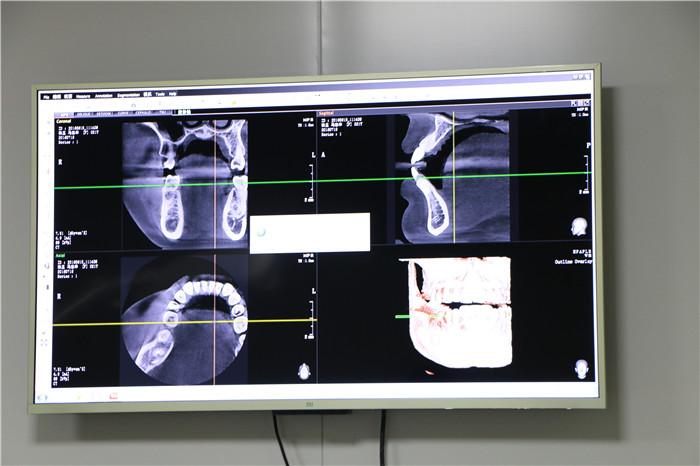

全景图

小编再给你们看下全景图~